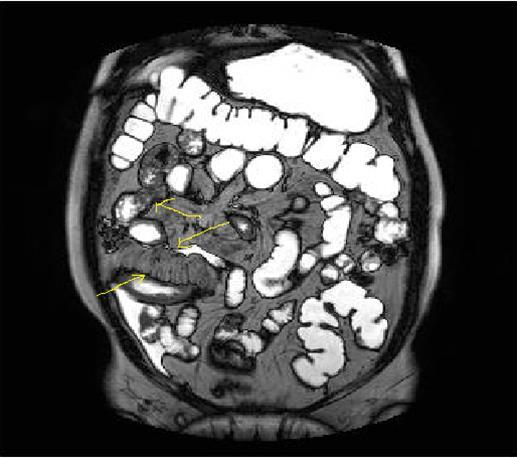

Figure 4a.Mucosal involvement and lack of opacified ileal segments with loss of intestinal folds and increased bowel wall thickness due to Crohn’s disease on T2W coronal sequence after OCA, presented at 37 years old male with moderate Crohn’s disease.

Figure 4b.Mucosal, luminal and bowel wall involvement in Crohn’s disease with skipped lesions, seen at T2W axial image after OCA, presented at 45 years old male with severe inflammatory disease.